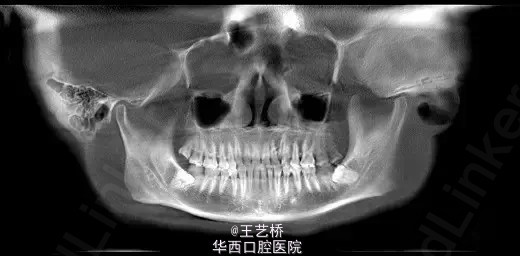

各式各样形态的上颌窦(一)

在进行上颌后牙区种植手术时,上颌窦形态是我们需要考虑吧的重要因素之一。今天收集了众多上颌窦的影像片,供大家交流学习。